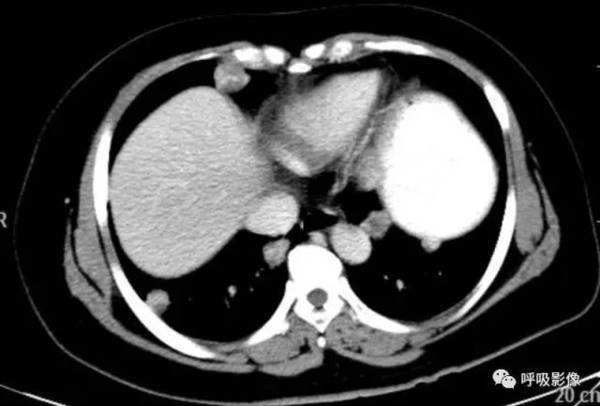

简单病史:女,35岁。查体发现肺部占位。胸部CT;右肺中叶外侧段近胸壁处圆形病变,边缘光滑,无毛刺, 增强扫描可见强化。

诊断依据: 青年女性,右肺中叶结节影,边缘光滑,密度均匀,无明显分叶、毛刺,临近胸膜无受累、肋骨无压迹,不符合肺恶性肿瘤诊断;患者无症状,不符合感染性疾病;病变密度均匀,内无坏死,无卫星灶,不符合结核球诊断。综合考虑肺良性肿瘤或孤立性转移瘤可能性大,病变位于胸膜下,孤立性转移瘤需考虑。病变增强扫描可见血管样强化,提示原发瘤血供丰富,最终病理为绒毛膜癌肺转移。